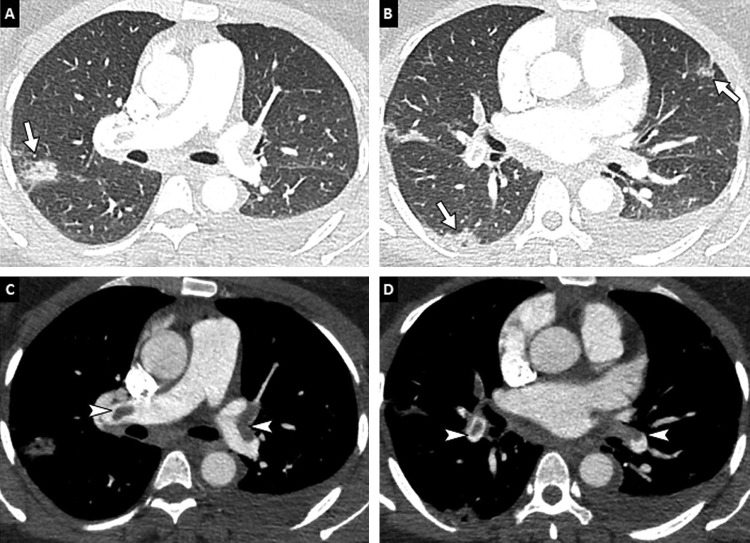

Pulmonary embolism has been reported in COVID-19 patients (Fig. 7 ) [35], [36], [37], [38]. In critically ill patients, there is an exacerbated systemic inflammatory response leading to a hypercoagulability state, reflected by the marked increase of D-dimer serum level in these patients [39]. The occurrence of pulmonary embolism is mainly reported in intensive care unit patients, based on retrospective studies. The exact prevalence of pulmonary embolism in COVID19 remains unknown, and would require a prospective evaluation, with systematic assessment of clinical symptoms, CT features and D-dimers. Routine CT pulmonary angiography to check for pulmonary embolism is so far not indicated as a first-line diagnostic tool. However, a clinical-radiological discordance (dyspnea and hypoxemia without lung abnormality) or respiratory worsening in a known COVID-19 patient should prompt the use of contrast medium injection. It would be worth assessing the value of routine CT pulmonary angiography in patients with highly elevated D-dimer levels. Finally, radiologists should be aware that pulmonary infarction secondary to pulmonary embolism may be quite similar in appearance to COVID-19 pneumonia (Fig. 8 ).

Fig. 7.

36-year-old woman positive for COVID-19 and pulmonary embolism. CT pulmonary angiography images in the axial (A, B) and coronal (C, D) planes show typical peripheral ground-glass areas related to COVID-19 pneumonia (arrows) and bilateral proximal pulmonary embolism (arrowheads).

Fig. 8.

74-year-old woman with COVID-19 pneumonia. (A, B) Baseline CT images obtained after intravenous administration of contrast material show peripheral ground-glass opacities (black arrowheads), bilateral proximal pulmonary embolism (white arrowheads) and a quadrangular well-demarcated subpleural consolidation containing central lucencies corresponding to a pulmonary infarction (arrow). (C, D) Follow-up CT images obtained 7 days later show progression of COVID-19 pulmonary lesions with reticulations, fibrotic streaks and architectural distortion (black arrowheads) and persisting thrombus (white arrowhead).